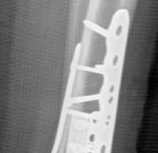

Fig 2.2-6a–b Immediate postoperative x-rays showing restoration of the ankle mortise and distal tibia alignment through anatomical and stable fracture fixation.

1. AP view.

2. Lateral view.